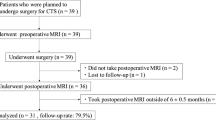

Radiomics was retrospectively done on peripheral nerve fascicles on T1-weighted 1.5T MRI of 40 patients with diagnosis of mild carpal (n = 25) and cubital tunnel (n = 15) syndrome and of 200 controls. Z-score normalization and Mann–Whitney U test were used to compare features of normal and pathological peripheral nerves. Receiver operating characteristic analysis was performed.